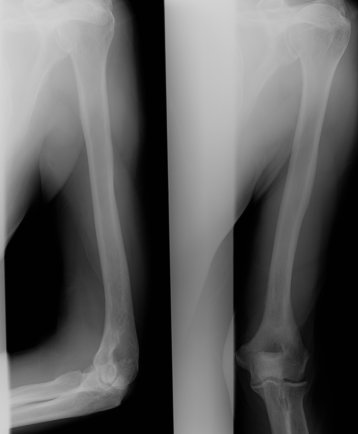

Return to Pathologic Fracture (Humerus)